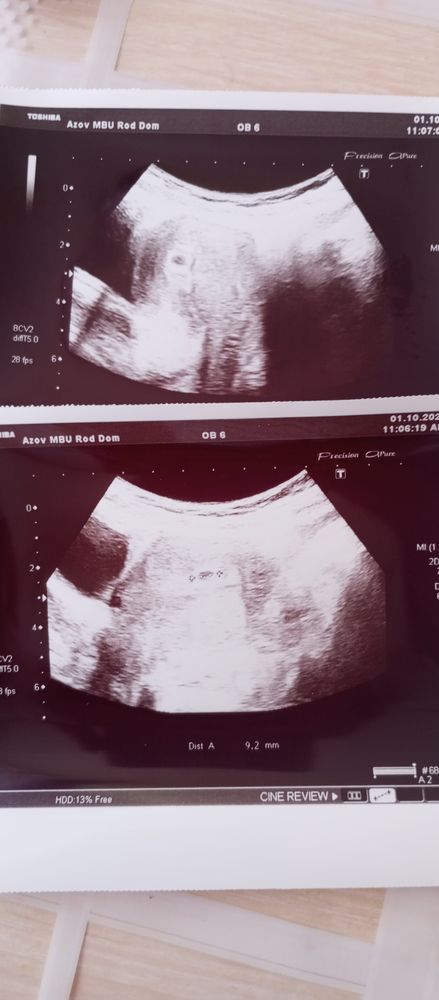

Девочки всем привет в субботу сдала хгч пришло 5524,сегодня пошла на УЗИ, увидели ПЯ 4 мл, срок 4 недели. Через пару недель можно увидеть будет эмбрион и услышать сердцебиение